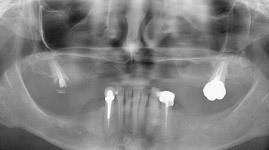

- Cas 2: vues panoramiques

AVANT REHABILITATION

PENDANT REHABILITATION 3 SECTEURS MOLAIRES